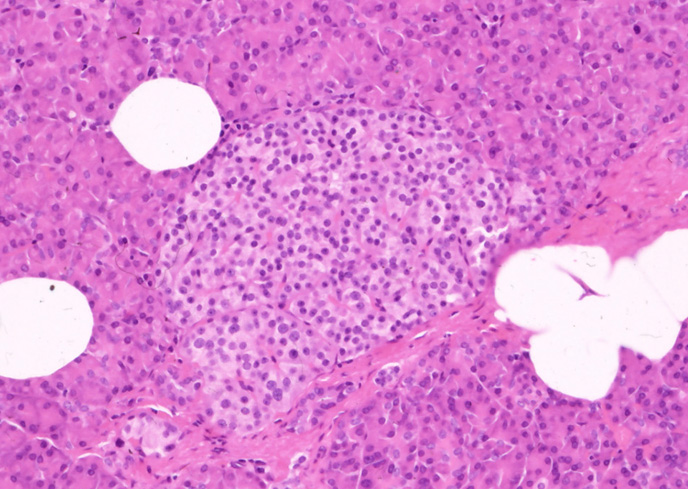

膵島(pancreatic islet, islets of Langerhans )*1

膵組織HE染色切片を光顕で観察すると周囲外分泌部に比べ淡染する島状の細胞集塊が容易に認められる。これが膵島で抗糖尿病因子(=インスリン)他のホルモンを分泌する重要な細胞を含む。

膵島は膵全体に広く散在し, とくに尾部に多い。形や大きさはさまざまである。一般には50-200μmの卵形ないし多角形で数十個から百個内外の細胞から構成されている。

膵島の腺細胞はB細胞, A細胞, D細胞と近年存在の知られたPP細胞に分けられる。これらの細胞は集簇して細胞索(立体的には板状構造)の網工を形成している。細胞索の間には毛細血管と少量の線維組織が介在している。